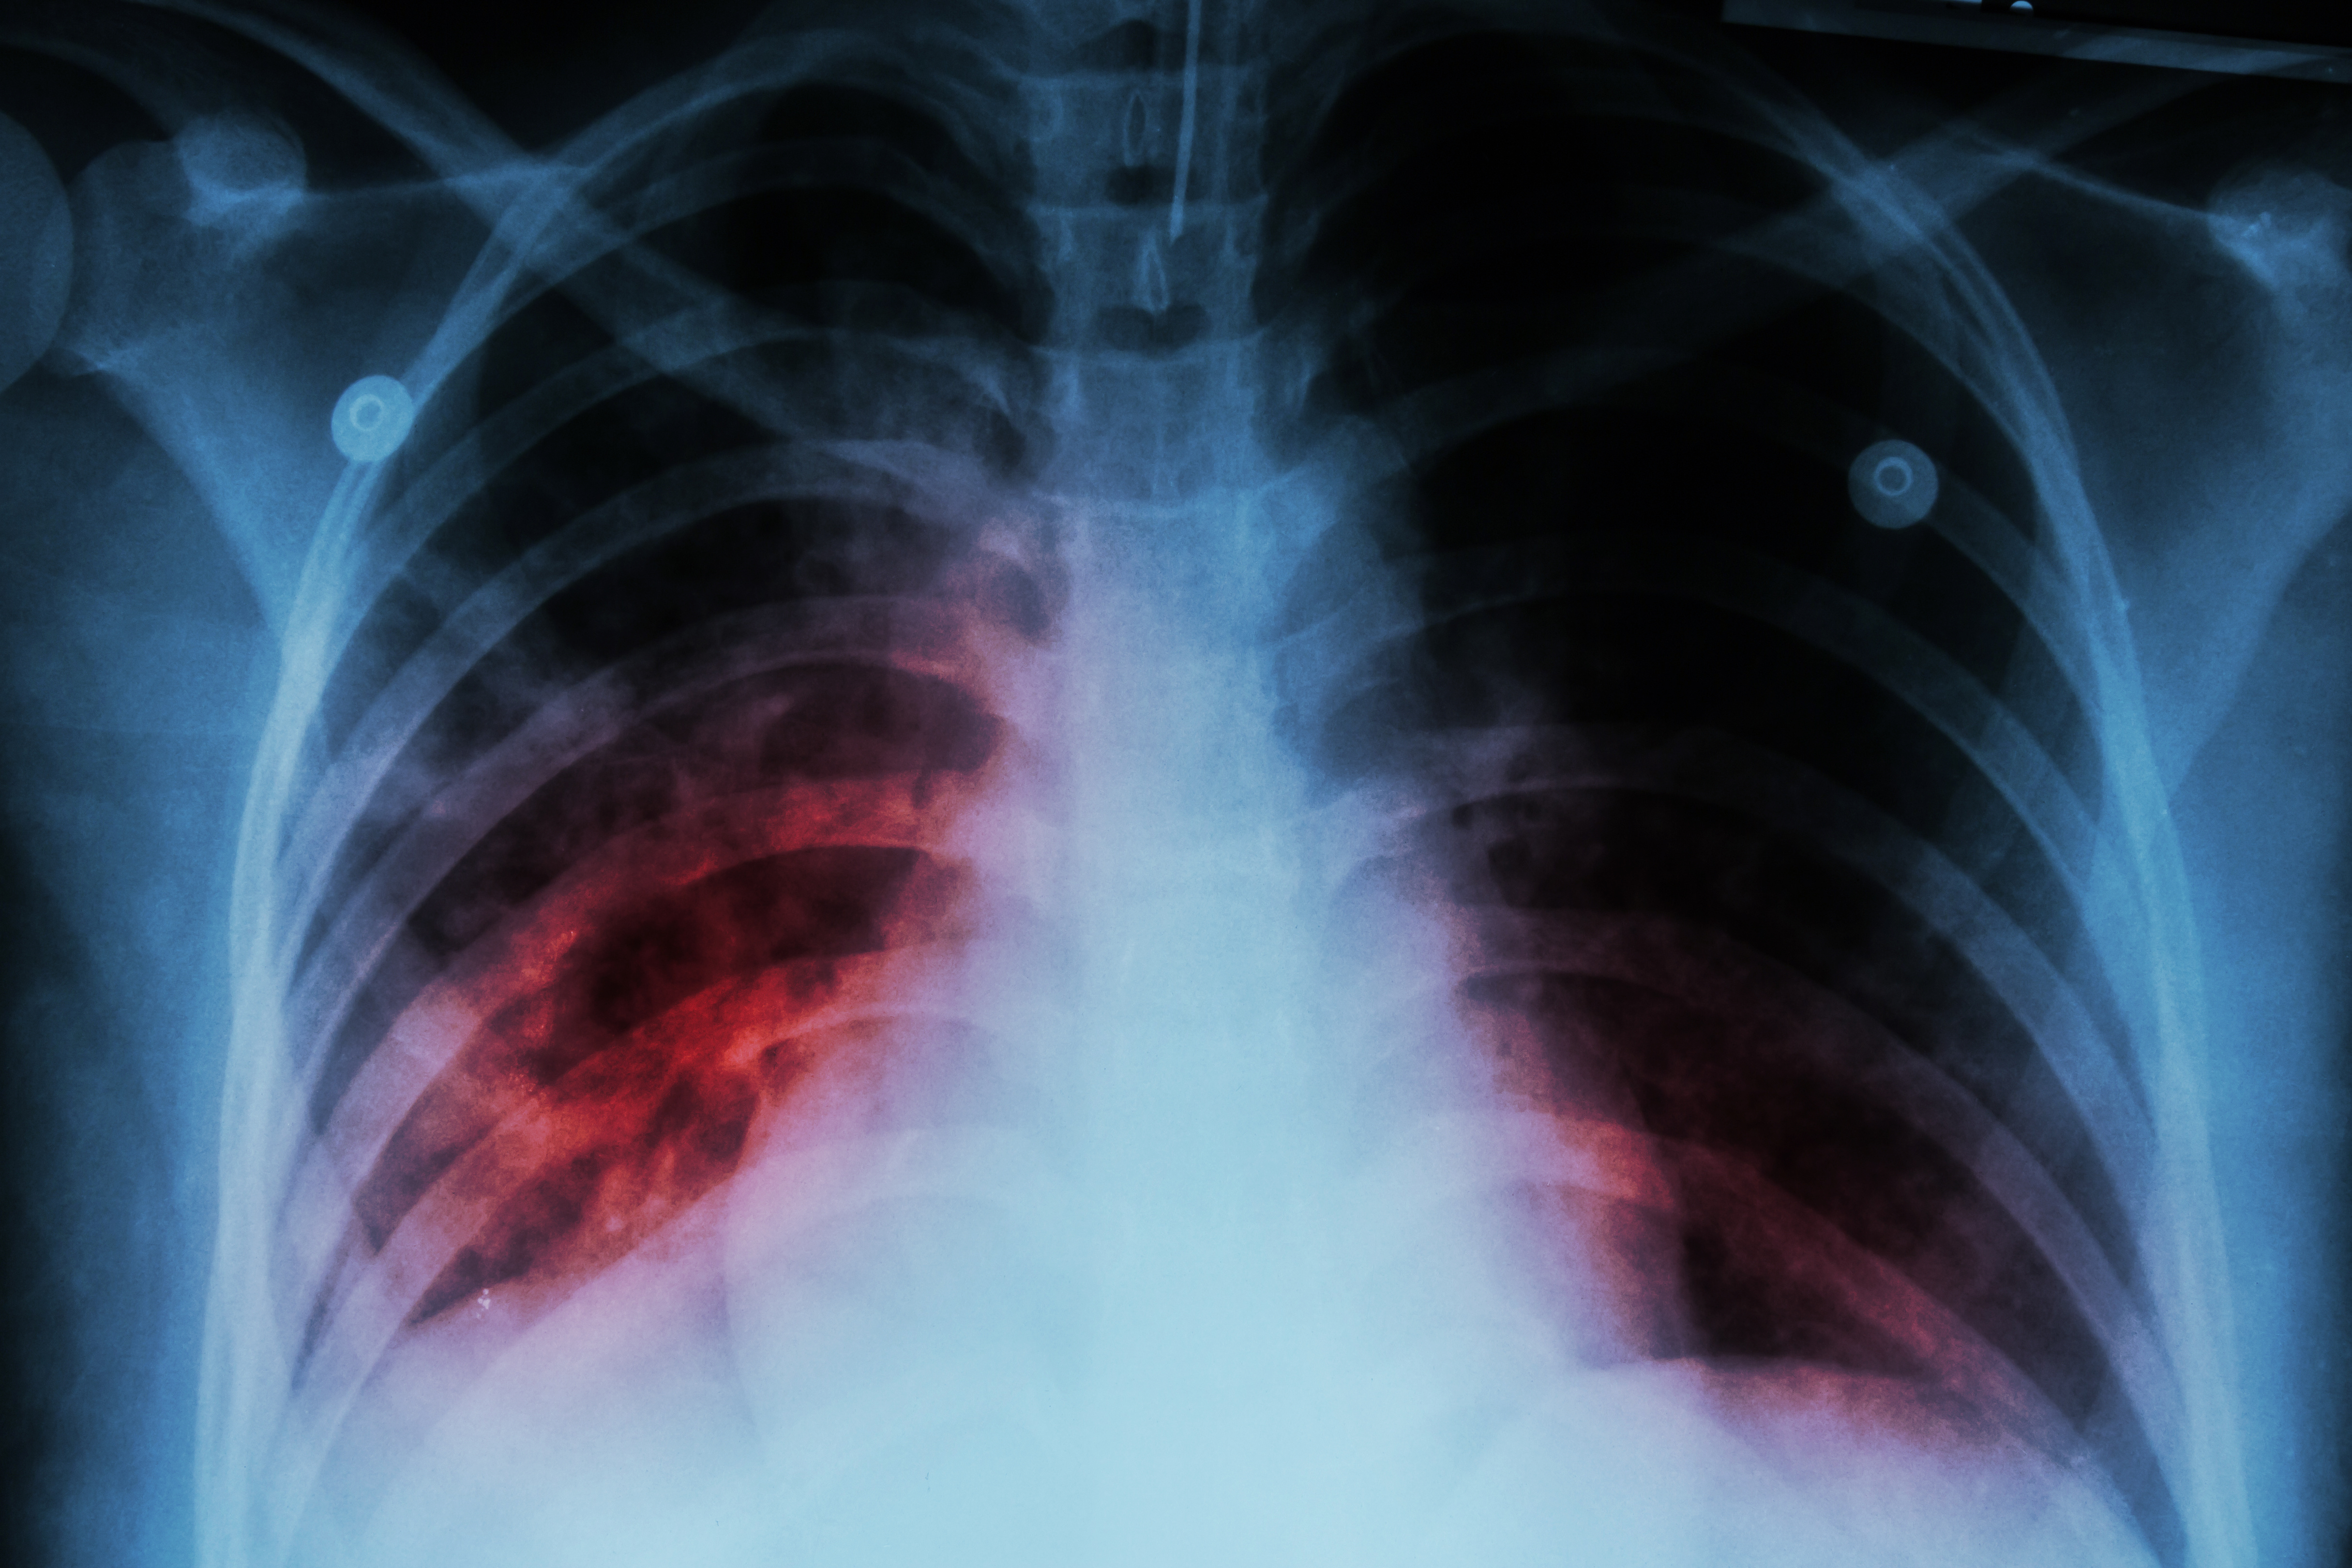

Dlaczego gruźlica nie zniknęła mimo postępów medycyny

Historia nauczycielki z Mrągowa, która tygodniami szukała przyczyny uporczywego kaszlu, odsłania niewygodną prawdę: gruźlica, choć rzadziej widoczna w statystykach niż choroby cywilizacyjne, pozostaje jedną z najbardziej uporczywych infekcji na świecie. Według WHO wciąż jest najbardziej zabójczą chorobą zakaźną na świecie.